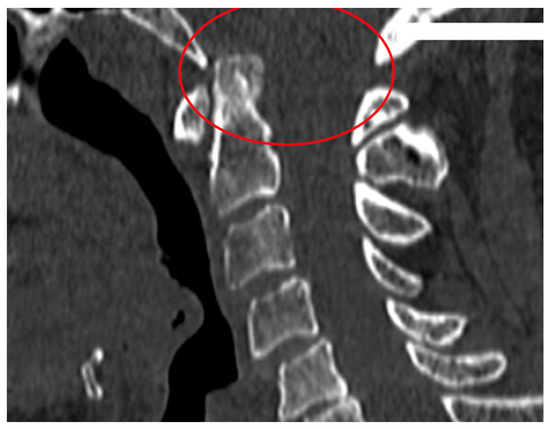

| AAS (atlantoaxial subluxation) | Weakening or rupture of ligaments and subchondral bone erosion in the atlantoaxial C1–C2 joints. |

| SAS (subaxial subluxation) | Subluxation in the joints C2–C7 due to destruction of the joint surface and the ligaments between the processes spinosis. |

| CS (cranial settling) | Vertical translocation of dens C0–C2 into the foramen magnum. |